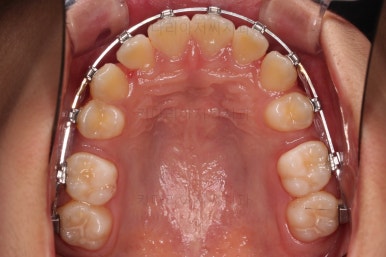

5. 마무리와 종료

부산치아교정치과 키다리아저씨치과에서 마무리한 입안의 모습입니다.

가지런하게 잘 정렬이 되었고요.

윗니만 발치한 편악발치교정이지만 틈새 없이 공간이 닫혔으며 교합도 잘 맞습니다.

간혹 윗니만 발치를 해서 윗니만 갯수가 적어 교합에 문제가 되지 않나요? 라는 질문을 하시는 경우가 있는데요.

윗니 아랫니는 1:1로 대응 되는게 아니라 지그재그로 서로 엇갈려 있기 때문에 특히 윗니는 하나 모자라도 교합에 전혀 문제 되지 않습니다.

위아랫니가 가지런하게 보기 좋게 배열이 되었고요.

아랫니까지 윗니를 넣음으로써 튀어나와 보이던 앞니의 느낌이 좋아졌습니다.

물론 작은 아래턱에 맞춰 윗니를 뒤로 집어넣어야 해서 자칫 지나치게 들어간 입이 될까 염려되는 조심스러운 케이스였지만, 편악발치를 통해 최소한으로 입을 넣으면서 굉장히 조화롭게 잘 마무리 했습니다.

웃을 때 보이는 앞니의 느낌과 위치가 참 좋아졌네요.

옆 라인도 움푹 들어가 있던 아랫입술 아랫 부분이 완만하게 펼쳐지면서 입매도 많이 좋아졌습니다.

이상 편악발치를 통한 돌출되어 보이던 앞니를 개선한 돌출입, 과개교합 교정치료 사례였습니다.